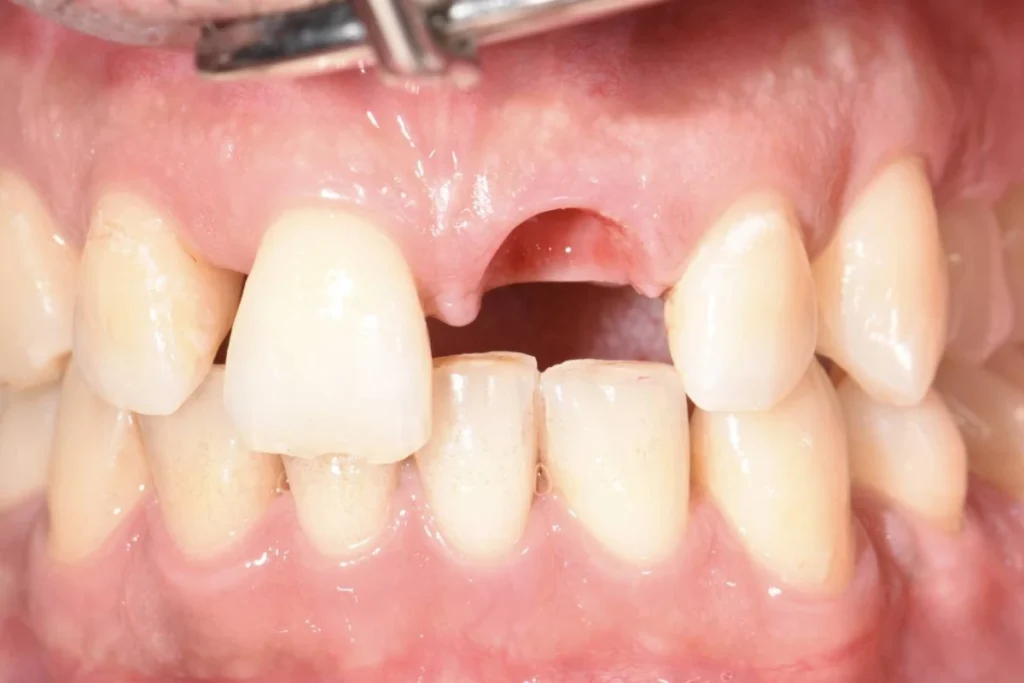

Mr M., 33 ans, se présente à la consultation suite à un traumatisme survenu à la boxe. La facette dentaire réalisée il y a plusieurs années par un confrère a été perdue après un coup encaissé au visage.

Le patient souhaite remplacer sa prothèse pour pallier au préjudice esthétique en urgence. Malheureusement, la dent présente une carie qui ne permet plus de conserver cette dent. Une dent provisoire est réalisée au cabinet afin de gérer l’urgence esthétique évidente et de permettre au patient de réfléchir aux soins proposés « à tête reposée » 🙂

Après un traitement parodontal initial nous permettant de mettre l’environnement buccal dans les meilleures conditions pour l’intervention, nous décidons avec le patient de planifier la chirurgie. Un protocole d’extraction implantation et mise en esthétique immédiate est décidé afin d’éviter au patient le port d’une prothèse amovible.

Le patient repart du cabinet avec une couronne fixée à l’implant tout juste mis en place! En contre partie, le patient devra faire l’effort de ne pas solliciter sa dent lors des repas afin de laisser l’implant s’ostéo intégrer (se souder) à l’os.